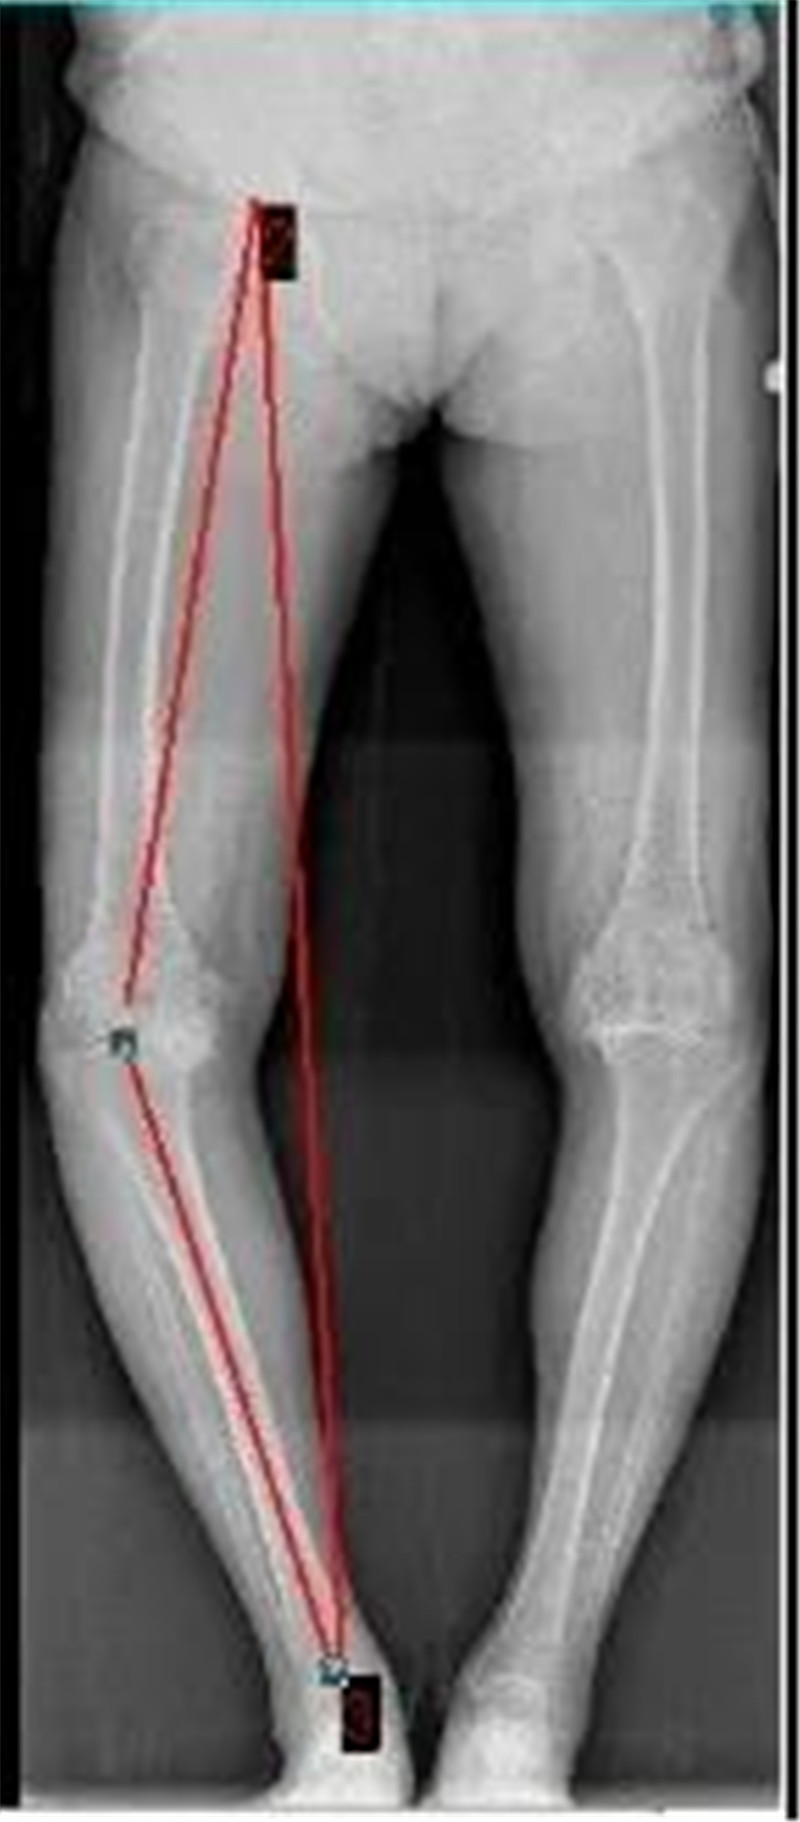

“X”型腿(外八字)和 “O”型腿(内八字)

O型腿矫正对比